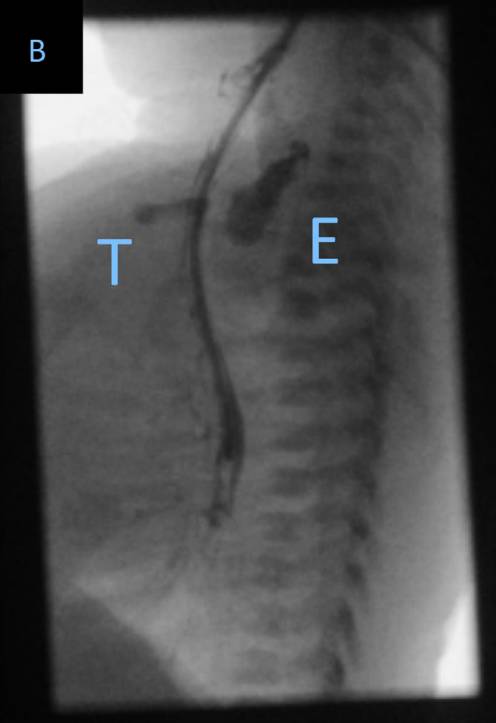

An 89-year-old woman was treated in our intensive care unit with Escherichia coli urosepsis. The patient developed multiple organ failure and became intubated and mechanically ventilated. On the third intensive care day, a new 16Fr. type “Levin” nasogastric tube was inserted for enteral feeding. As no anatomical abnormalities were described, we followed a blind insertion technique, encountering no resistance while advancing the tube towards the stomach, and final position was confirmed by auscultation of a gurgling noise over the epigastrium. Enteral nutrition was started, according to ICU feeding protocol. However, 48 h later, acute hemodynamic instability was observed and invasive mechanical ventilation became difficult. A bed-side ultrasonography showed a pleural effusion on the right side, and a puncture for pleural-catheter placement revealed nutrition in the pleural space. 3D-reconstructed images of a chest computed tomography (Fig. 1a, arrow) demonstrated the endpoint of the nasogastric tube into the right pleura, confirming the perforation of the right lower lobe bronchus and massive lung parenchyma damage (Fig. 1b), despite the patient having an endotracheal tube in situ and giving no signal of cuff insufficiency. We suggest that radiological control remains the standard procedure to confirm the correct position of a nasogastric tube, even by invasive ventilated patients.

一名89岁女性患者因大肠杆菌泌尿系感染导致sepsis在ICU接受治疗。患者出现多器官功能衰竭,接受气管插管和机械通气。入住ICU的第三天,置入16 F的Levin型鼻胃管进行肠内营养。由于未发现任何解剖学异常,我们采用盲法置入,将鼻胃管送入胃内时未遇到任何阻力,置管结束后在上腹部听诊到气过水声确认导管位置。根据ICU喂养方案开始肠内营养。然而,48小时后,患者出现血流动力学不稳定,有创机械通气难以维持。床旁超声检查显示右侧胸腔积液,置入胸腔引流管发现胸腔积液为营养液。胸部CT检查三维重建(图1a,箭头)显示鼻胃管末端位于右侧胸腔内,确诊右下叶支气管穿孔及大面积肺实质损害(图1b)(尽管患者有气管插管且没有套囊漏气的表现)。我们建议,即使对于接受有创机械通气的患者,影像学检查仍然是确认鼻胃管位置正确与否的标准措施。

一个足月的新生儿在出生后出现了呼吸困难的症状,为了进一步支持治疗,大夫决定给患儿下一根鼻胃管。放置的过程比较顺利顺利进入相应深度之后,拍了一个胸片确认鼻胃管位置(图A)。

怎么拔鼻腔引流管胃管术(二)_https://www.jmylbn.com_新闻资讯_第49张

从胸片上来看,鼻胃管的一端顺利抵达了胃中,这是一次顺利、正确的插胃管。

然而,仅仅过了不久,患儿就出现了呼吸困难加重、经口喂养不耐受等症状,这是为什么呢?

经过进一步检查,大夫怀疑患儿有先天性的食管闭锁,但是从上图看,鼻胃管明明已经下到胃中了啊,这又是为什么呢?

为了探究这个奇怪的现象,他们给患儿行了进一步的检查,利用对比剂重新进行胸部影像学检查,结果如下(图B):

怎么拔鼻腔引流管胃管术(二)_https://www.jmylbn.com_新闻资讯_第50张

看完这次影像学检查后,大夫终于恍然大悟,原来如此。